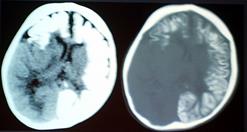

Рис. 35 (а, б). а – КТ-томограмма без патологических изменений;

б – кистозная опухоль лобной доли у ребенка 1 года.